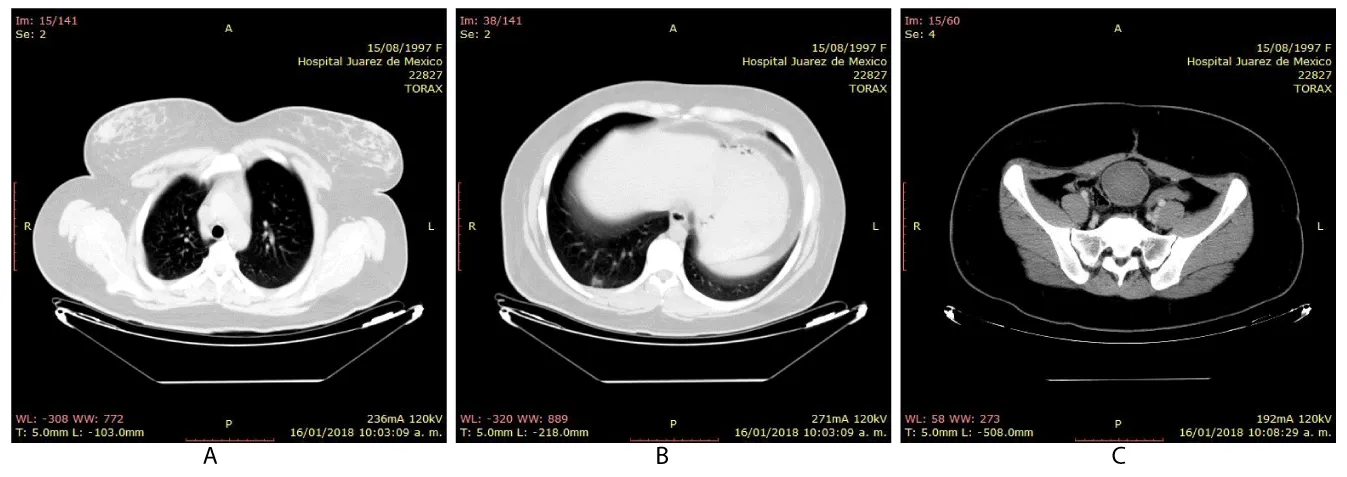

On physical examination, the patient with generalized pallor of the skin and integuments, hypotensive, tachycardic, diaphoretic, without cardiorespiratory compromise, globose abdomen due to abundant adipose panniculus, perstalsis present, pain on palpation in the right iliac fossa on bimanual touch, the uterus is delimited 8x5 cm, right annex, 12x9 cm adnexal tumor, irregular, firm, pain on cervical mobilization, with spotting-shaped transvaginal hemorrhage, extremities without edema, normal tendon reflexes. According to the clinical presentation, imaging studies, on suspicion of ruling out ectopic pregnancy, an exploratory laparotomy was performed, with findings of the right annex of 20x15 cm adhered to the uterus and sigmoid rectum without evidence of hemoperitoneum and a right salpingo-oophorectomy was performed for probable right ectopic pregnancy with hematic loss due to the surgical procedure of 40cc and sent to pathology for definitive histopathological study, during follow-up a control gonadotropin quantification was requested with the last report of 1 103 918.7 mUI/mL. The histopathological results of the macroscopic surgical specimen were right salpingo-oophorectomy, with choriocarcinoma with extensive necrosis, 1 cm tumor extension to the ovarian surface not identified, lymphovascular invasion present and free surgical margins of the residual ovarian tumor with cystic follicles, Figure 1 and the report microscopic, Figures 2-4. A new hCG quantification is performed, negative head tomography and chest tomography with probable metastasis due to pulmonary nodule, in abdomen and pelvis, presence of peritoneal carcinomatosis, with free fluid and lumbar puncture reports negative for malignant cells and chemotherapy based on cisplatin and etoposide 5 sessions and the patient is disease-free after two years of follow-up.

Choriocarcinomas, due to their great angioinvasion capacity, which facilitates their dissemination and encourages metastases to the lung, brain, liver and other organs, have early metastasis to the lung even in 80% of cases, in our case, pulmonary metastasis was diagnosed by imaging, confirming the great tumor vascular invasion; the majority die, even when diagnosed early to initiate appropriate chemotherapy, with a mortality rate of 10% to 15% [17,18]. This report describes a case that simulated an ectopic pregnancy, which underwent surgery of the administration of chemotherapy; We report that the reproductive prognosis is favorable and treatment with conservative surgery does not affect fertility. Ovarian germ cell malignancies are sometimes associated with pregnancy or term pregnancies are achieved after uncomplicated treatment with healthy term infants [19].

The tumor has a marked tendency to metastasize early by dissemination to the blood, lungs (80%), pelvis (20%), vagina (30%), liver (10%) and other rare sites gastrointestinal tract, spleen and kidney; the central nervous system is rarely involved in the absence of pulmonary metastases; but, it is one of the main causes of death. Metastases are commonly hemorrhagic due to the innate ability of trophoblastic cells to invade and erode blood vessels [26].